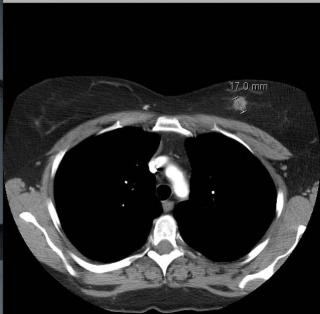

Одним из дополнительных методов изучения грудных желез, используемым для уточнения диагноза и контроля успешности лечения, служит компьютерная томография. Как правило, ее назначают лишь в том случае, когда основные исследования – маммография и УЗИ – не принесли полной ясности и оставили определенные сомнения.

КТ молочных желез необходима для уточнения размеров обнаруженной ранее опухоли и степени ее прорастания в структуры грудной клетки, для поиска метастазов из других органов, а также для оценки изменений после проведенной терапии.

Компьютерная томография (КТ) на уникальном оборудовании последнего поколения для точной постановки диагноза

Единственный в Москве компьютерный томограф Revolution CT (GE), 512 срезов

Основной причиной для назначения КТ молочных желез является обнаруженная в тканях груди опухоль. Задачей диагностики является:

• точная локализация злокачественного новообразования;

• оценка размеров и степени разрастания патологической ткани;

• обнаружение метастазов и кальцинатов в близлежащих лимфоузлах и соседних органах;

• выявление патологических образований в местах, которые сложно обследовать другими методами;

• обнаружение воспалений, травм мягких тканей, проверка целостности грудных имплантов.

Для КТ молочной железы клиника применяет современное диагностическое оборудование – томографы Somatom Definition и Revolution CT, использующие мультиспиральную технологию сканирования. Она заключается в одновременном движении нескольких излучателей и датчиков, просвечивающих ткани под разными углами. Это позволяет обеспечить максимально точный и информативный результат. Кроме того, габариты оборудования исключают ограничения пациентов по весу и объему тела.

Показания датчиков томографа обрабатываются компьютером и преобразуются в высокоточное объемное изображение тканей молочных желез. Оно отчетливо выявляет структуру жировых и железистых тканей, молочных протоков, лимфоузлов, кровеносных сосудов, а также прилегающих хрящевых образований и костей.